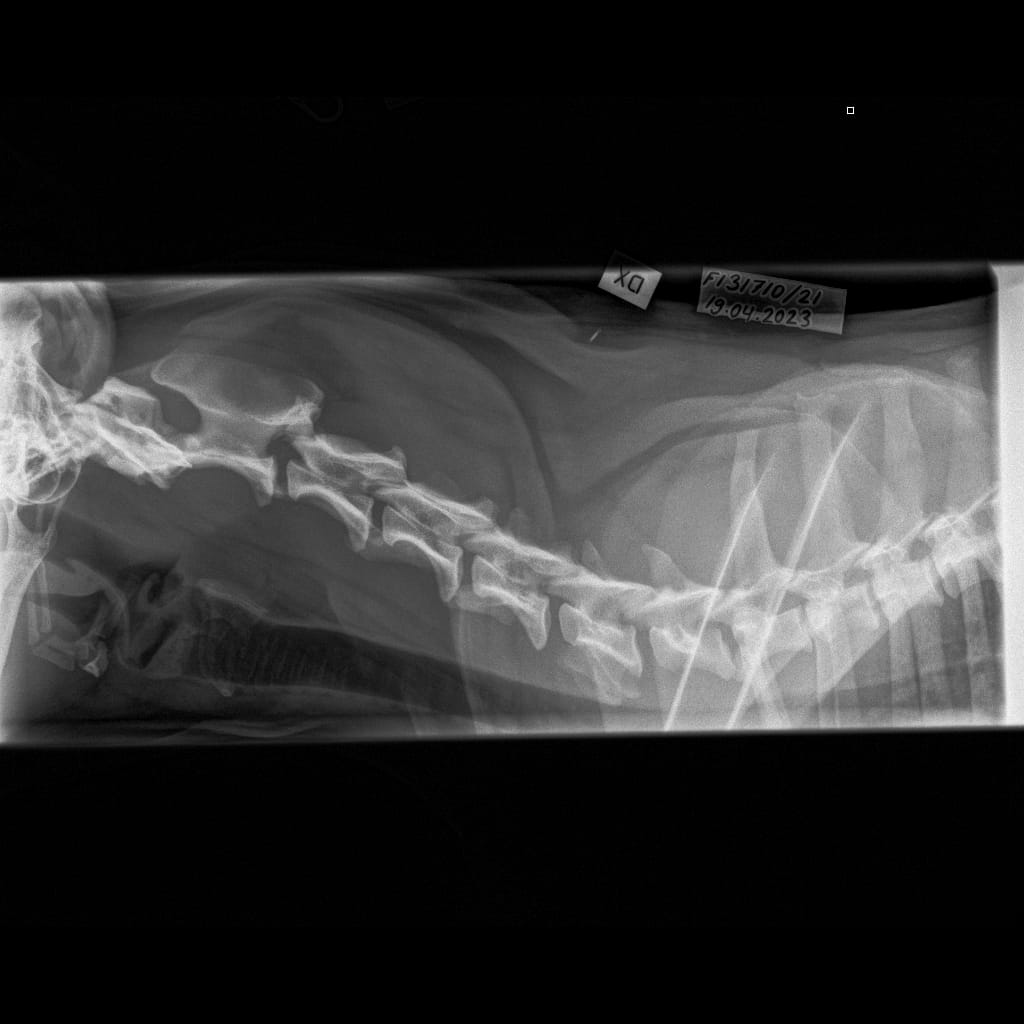

Selkäranka -Kaularanka LAT-6.11.2023-16_02_20-906